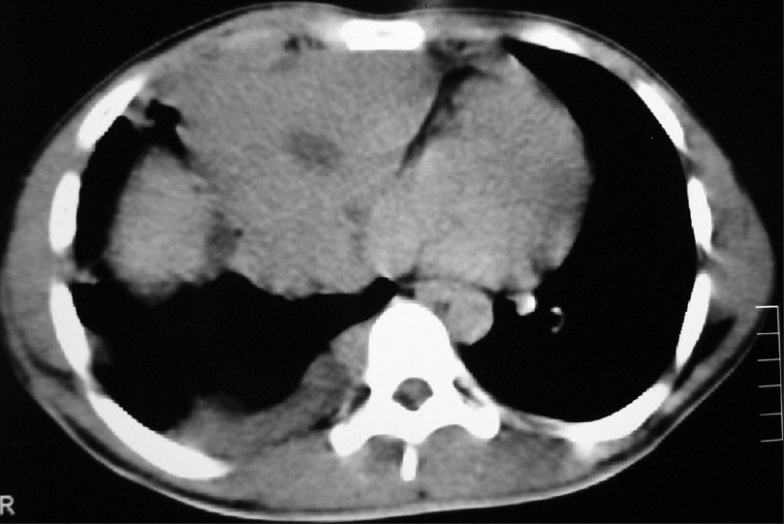

CECT chest showed anterior mediastinal mass with extension into right side of chest [Figure 2]. Image-guided biopsy of the lesion was done. The results did not reveal malignancy. Cardiothoracic surgeons proceeded with right thoracotomy and excision of the mass. Histopathology of the specimen showed seminoma of thymus [Figures [Figures33 and and4].4]. The result of the test for placental alkaline phosphatase was positive [Figure 5]. The patient failed to follow up for 8 months as he was asymptomatic.

| Figure 2 CT chest (2006 ) shows anterior mediastinal mass extending into right side of chest